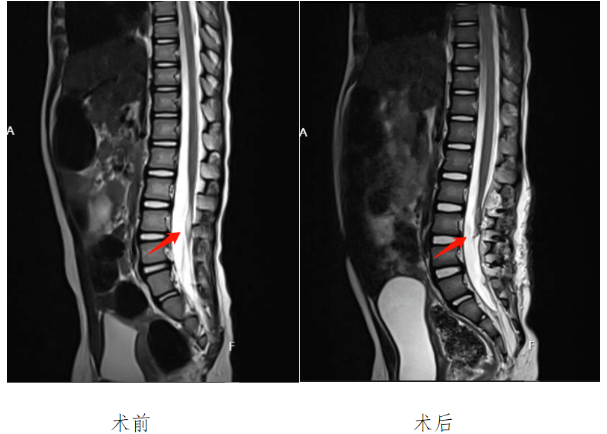

但神经脊髓像豆腐、细面条一样软,神经被裹到脂肪里很难梳理开,既要将脂肪瘤去除,又要避免损伤神经,手术风险极大。当脊髓与脂肪粘连,只要有一点没被松解开,脊髓栓系就不能解除。所以手术的目标一定是脊髓“完全松解,彻底游离,防止粘连”,对术者技术要求极高。为确保手术顺利进行,能够最大程度保证患儿术后的健康成长,林志雄教授、神经外科张金锋主任组织科室团队多次对患者病情进行分析,解释疑点,最终制定了周密的治疗方案。征得患者家属同意后,林志雄教授与张金锋博士主刀,张朋医生作为主要助手,为患儿实施电生理监测下脊髓栓系松解术+椎管内脂肪瘤切除术+终丝离断术。

手术如期举行,术中全程神经监测,孩子的神经根都非常纤细,稍不注意神经根就会被碰断,对术者的精细操作要求很高,脂肪瘤与脊髓、神经根粘连包裹,终丝发育不明显且与神经根混合在一起,在神经电生理监测下用刺激器反复确认神经根并加以保护,顺利切除脂肪瘤,脊髓、神经根予以粘连松解,手术顺利完成。术后及时予抗感染,提早康复锻炼,促进神经修复治疗等严密监测,精准治疗,小齐齐才渐渐康复,近日出院了。整天提心吊胆的家人,终于松了一口气。